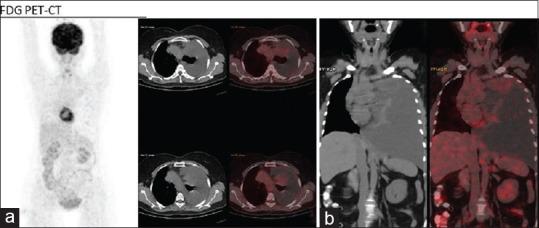

We present a rare case of mediastinal capillary hemangioma in a 54-year-old female. She presented with back pain in the left suprascapular region, and the chest radiograph revealed left pleural effusion. On further workup with high-resolution computed tomography (CT) chest, a hypervascular pleural-based neoplastic lesion in the left upper hemithorax with gross left pleural effusion and subtotal collapse of the left lung was identified. F-fluorodeoxyglucose positron emission tomography/CT was suggestive of a weakly metabolic well-defined pleural-based soft tissue lesion in the left upper hemithorax along the mediastinal side. Neuroendocrine tumor was suspected. Ga-DOTATATE PET/CT was advised, which showed intense uptake in the lesion. The mass was resected completely. Histopathological examination established the final diagnosis as benign vascular tumor consistent with a capillary hemangioma.

我们报告一例54岁女性纵隔毛细血管瘤的罕见病例。她表现为左肩胛上区背痛,胸部X线片显示左侧胸腔积液。进一步行胸部高分辨率计算机断层扫描(CT)检查时,发现左上半胸有一个以胸膜为基底的高血管性肿瘤病变,伴有大量左侧胸腔积液及左肺部分萎陷。氟脱氧葡萄糖正电子发射断层扫描/CT提示左上半胸纵隔侧有一个代谢较弱、边界清晰的以胸膜为基底的软组织病变。怀疑为神经内分泌肿瘤。建议行镓- DOTATATE PET/CT检查,结果显示病变部位有强烈摄取。肿瘤被完整切除。组织病理学检查最终确诊为与毛细血管瘤相符的良性血管肿瘤。